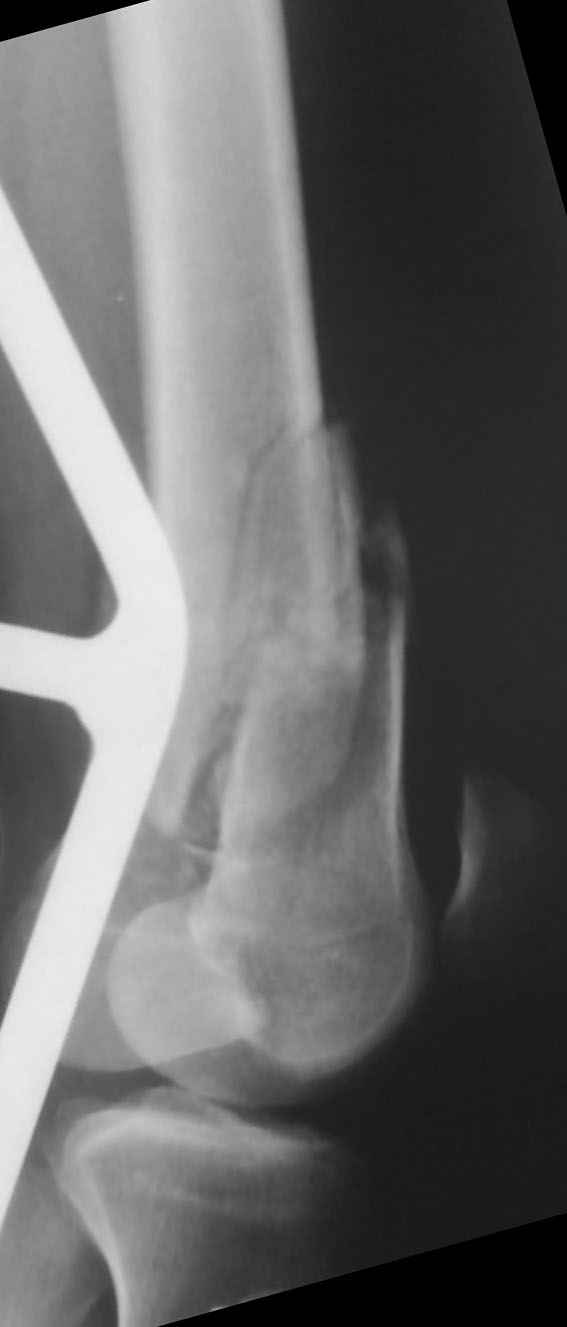

Уважаемые коллеги! От имени Алексея Смирнова всем спасибо за обсуждение. Больной прооперирован. Снимки в приложении.

Привет из Нижнего Новгорода! К нам поступил пациент 25 лет с закрытыми переломами обеих бедренных костей, прошел месяц после травмы. Слева - внутрисуставной перелом, поэтому выбор здесь очевиден, открытая репозиция, стабильная фиксация, скорее всего LCP DF, а справа - мнения учёных, как говорится, разошлись. Лично я, как лечащий врач, за закрытый интрамедуллярный остеосинтез DFN. Со мной согласна половина коллектива, другая - за интрамедуллярный остеосинтез (DFN,UFN) но с открытой реопозицией, поскольку при закрытой методике все осколки останутся где-то сбоку, получится дефект и вдруг не срастется!Философский вопрос: что лучше - красивая рентгенограмма или сохранение кровоснабжения? Очень важно мнение коллег! Смирнов Алексей

Приветствую всех коллег!!Во первых слева хотелось бы видеть четкую боковую проекцию а лучше КТ. По р-мам есть сомнения насчет повреждения суставной поверхности. При подобных переломах даже внутрисуставных без смещения хорошие результаты показал закрытый ретроградный остеосинтез универсальным бедренным стержнем Деост.Кстати при внутрисуставном переломе возможно применение вместо винтов стягивающих болтов!!(См. метод.Деост).При переломе справа также стержень Деост. Однако без открытия Вам не удастся устранить интерпозицию, только промучаетесь!Из минимального разреза удалите интерпозициб и фиксируйте стержнем. Причем универсальный стежень Деост позволяет фиксировать дистально минимум на трех уровнях!